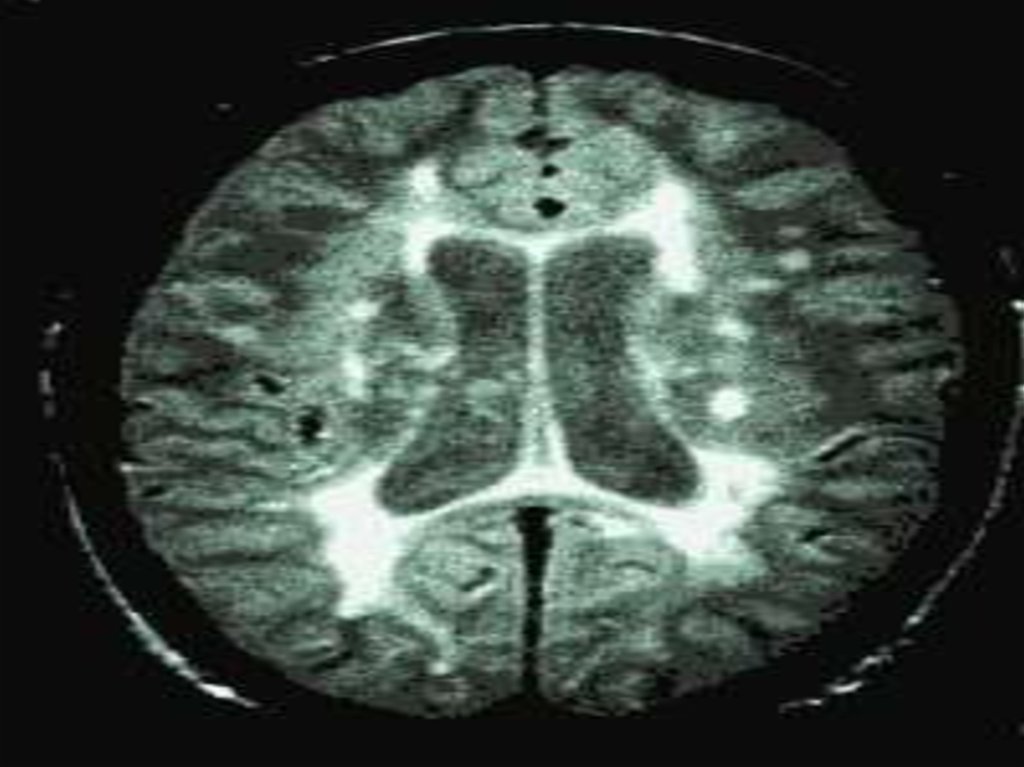

Рассеянный склероз (РС) – хроническое, прогрессирующее

заболевание центральной нервной системы,

патоморфологическую основу которого составляют

процессы демиелинизации нервных проводников

(распад миелиновой оболочки) в головном и спинном

мозге. Клинически РС характеризуется рассеянной

неврологической симптоматикой, слагающейся из

преимущественного поражения оптической,

пирамидной и мозжечковой систем головного и

спинного мозга. В большинстве случаев, особенно на

начальной стадии, течение заболевания

ремиттирующее с последующим переходом в медленнопрогредиентное. Дебютирует РС в молодом возрасте

(20-40 лет), однако не исключается возникновение

заболевания у детей и лиц старше 50 лет.